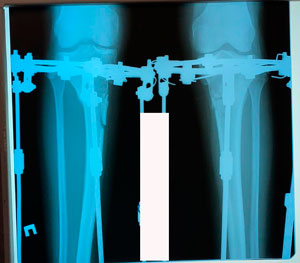

перед крутками

Вложения

image-24-03-20-12-02.jpg